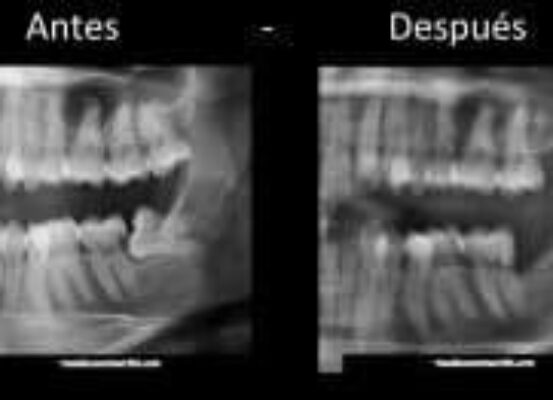

Lesión de caries como consecuencia de tercer molar impactado

La impactación dentaria es una situación patológica en que un diente está total o parcialmente incluido en el maxilar – es decir, que podría o no verse en boca- y que se encuentra posicionado contra e